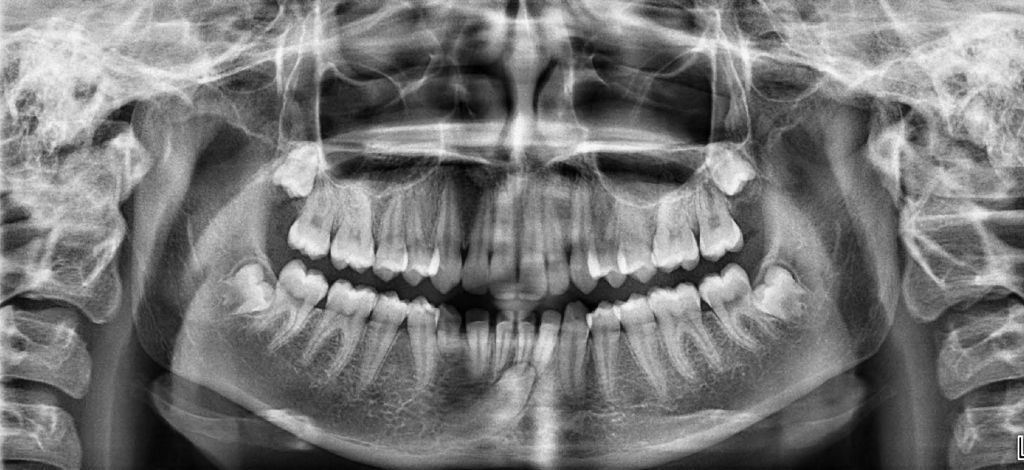

Exemple radiologique d’une canine mandibulaire incluse, avec migration vers le côté opposé.

Il arrive que, par la suite de la chute d’une dent de lait, ou même plus tôt, une dent définitive ne fasse pas éruption de manière naturelle. On parle de rétention dans un premier temps, puis d’inclusion, voire d’ankylose.

Les dents les plus sujettes à cette évolution pathologique sont les canines, dont l’apparition normale en bouche se situe autour de l’âge de 10-11 ans. Il s’agit d’une anomalie de la croissance et du développement facial, dont l’incidence, selon les études, s’établit entre 1 et 2,5%.

Les causes sont variées, aléatoires et imprédictibles: obstruction anatomique des tissus durs, lésions muqueuses, anomalies anatomiques de la canine maxillaire elle-même ou dents contiguës, facteurs génétiques probables, antécédent traumatologique, ou une association de ces causes aboutissant à un milieu biologique propice.

Un diagnostic clinique précoce est donc fondamental, dès l’âge de 8 à 10 ans, ce qui permet de réduire significativement les complications, notamment la nécessité d’une prise en charge orthodontique avec chirurgie d’exposition.

Le traitement de désinclusion primaire consiste en une orthodontie conventionnelle afin de créer de l’espace sur l’arcade. Une étude portant sur 28 adolescents âgés de 11,4 à 16,1 ans, ayant une canine maxillaire incluse, a montré que l’orthodontie seule aboutit à une mise place sur l’arcade dans 75% des cas, le reste devenant des indications d’exposition chirurgicale avec traction.

En dépit de prises en charge correctes, les échecs demeurent fréquents. Une étude réalisée sur un échantillon de 37 canines maxillaires incluses ayant résisté à la désinclusion a montré que les tentatives infructueuses avaient pu s’étendre sur une durée allant de seulement 9 mois jusqu’à plus de 3 ans et demi.

En cas d’échec, ou de diagnostic trop tardif, l’alternative est souvent l’extraction de la dent incluse et une approche prothétique de la restauration de la fonction et du sourire.

Conseil: un enfant entre 6 et 12 ans devrait toujours être présenté au dentiste tous les 6 mois, afin de vérifier l’harmonie et la bonne chronologie du remplacement des dents de lait par les dents définitives, ce qui impose un examen et des radiographies régulières.